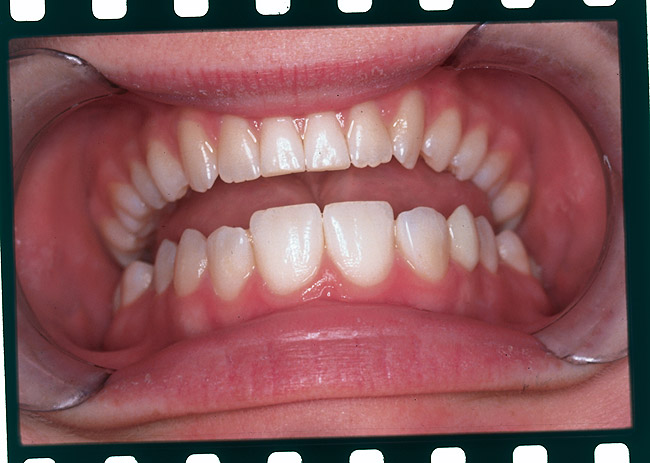

Figure 1 A patient presents after completion of orthodontic treatment for restorative enhancement of microdontic maxillary lateral incisors.

Figure 1